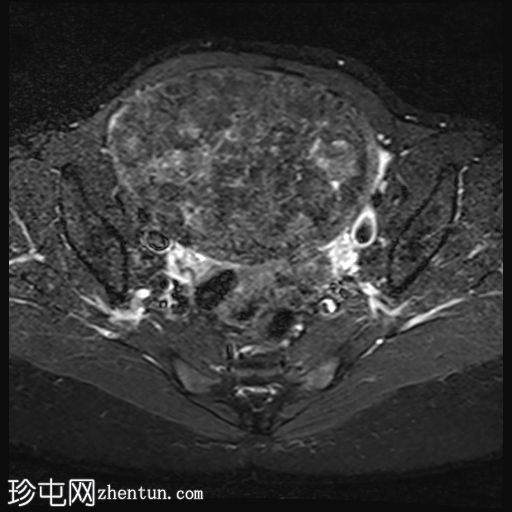

子宫后壁可见一个边界清晰、体积较大的浆膜下肌瘤,大小约为16.1 x 10.5 x 14.4 cm(宽 x 深 x 高)。

该肌瘤在T1加权像上呈中等信号,在T2加权像上呈低信号,内部区域呈囊性变性。

该肿块导致正常子宫结构严重变形。增强扫描显示轻度不均匀强化,未见弥散受限征象或提示恶性肿瘤的可疑强化。

双侧卵巢增大,各有超过10个卵泡,呈珍珠串状排列,周围未见优势卵泡。这些发现符合多囊卵巢的形态学特征。